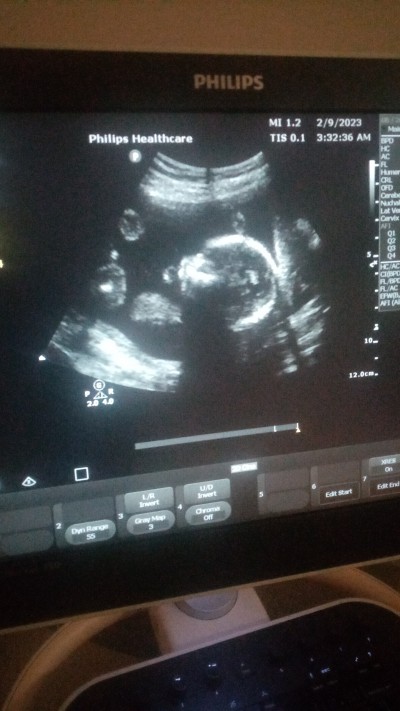

Özel doktr plesenta yanda duruyor ilişki yasak dedi, devlet ise plesenta arka tarafta iyi yerde ilişki olabilir dedi, resimden anlayan varmı sizce hangisini dnlicez sadece kafası gorunuo kolu bacağı nerde bu bebegn ya, hiç bı hareketini de his etmiorm daha

Gebelik haftası 18+6

Benim plesanta asagidaydi bebeğin yanaklarinin yanında duruyordu ultrosan kağıdında seninki kafanın arkasında gibi sanki tabi ben bilememde bana öyle geldi benimkiyle kıyaslayınca sen kesinlesmeden ilişki yapma kanaman gelir sonra birdahaki gidişinde kesinlessin öyle hareket et